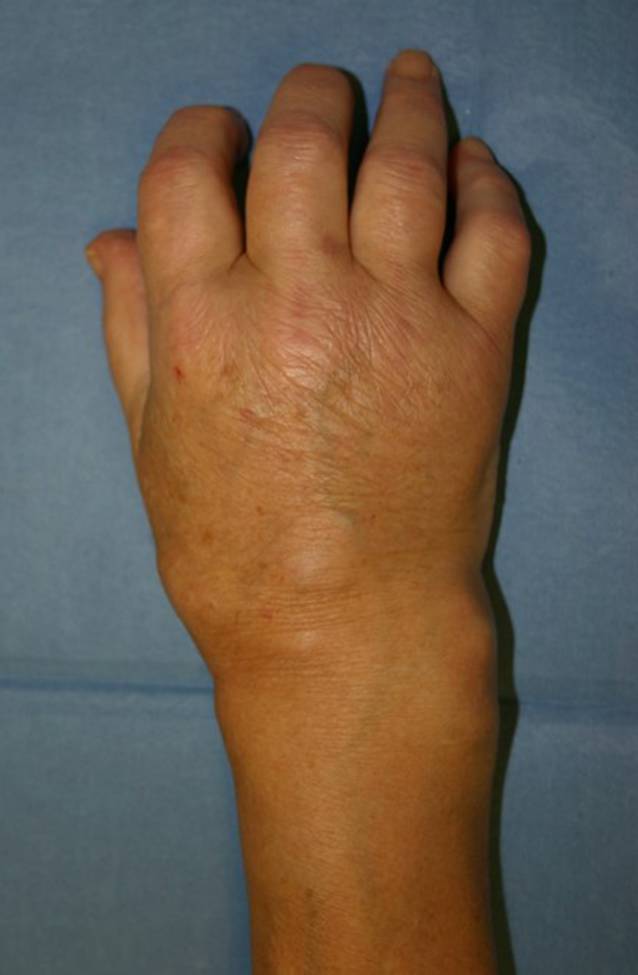

Radiologie

Im Röntgenbild des Handgelenks in 2 Ebenen und der Magnetresonanztomographie zeigten sich eine Osteitis des distalen Unterarms und gesamten Carpus mit deutlichen Erosionen sowie eine Handgelenksynovialitis. Zusätzlich bestand eine Synovialitis im Bereich der Strecksehnenfächer (Abb. 2).

Abb. 2

a Im Röntgenbild Osteitis des distalen Unterarms und des gesamten Carpus mit Erosionen. b Im MRT (T1-Wichtung, fatsat) zusätzlich Synovialitis im Bereich der Strecksehnenfächer